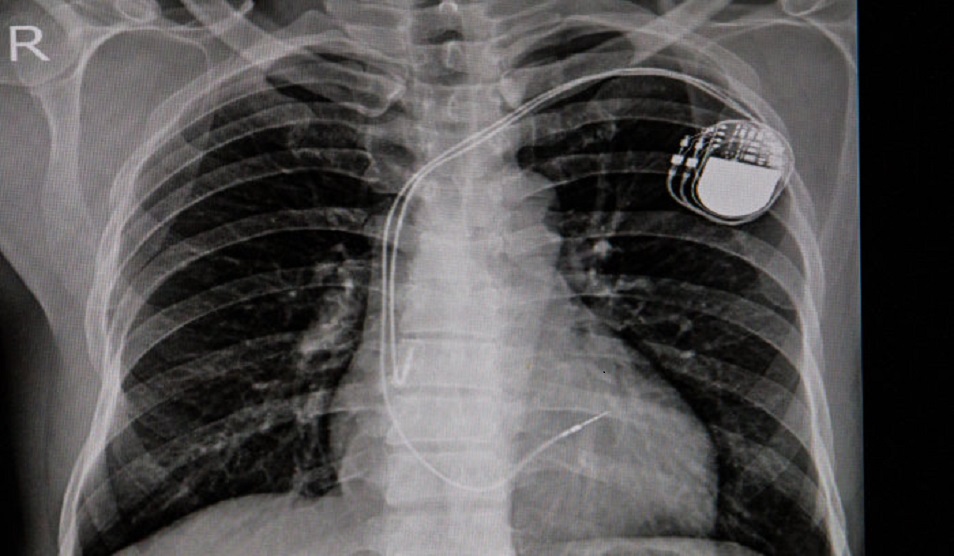

- pacemakers for bradyarrhythmias

- complex devices — implantable cardioverter-defibrillators (ICD) and cardiac resynchronisation therapy (CRT)

- Having a pacemaker implantation

- Having an implantable cardioverter defibrillator

We offer a number of treatments for heart rhythm disorders, including pacemakers and implantable cardioverter defibrillator (ICD). The British Heart Foundation has created videos to help explain what those devices are and how they work. If you have any questions, please raise them with your consultant when you come to hospital.

Pacemaker